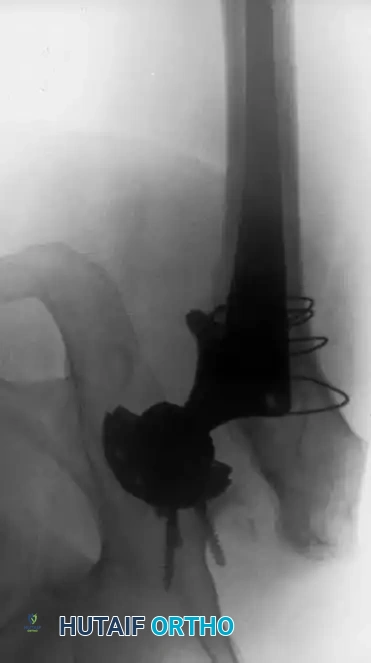

2. Modular Fluted Tapered Stems: The modern workhorse for severe (Type III and IV) defects. The flutes provide rotational stability, while the 2-to-3 degree taper achieves axial stability via three-point fixation in the diaphysis. Modularity allows independent adjustment of version, offset, and leg length after the distal stem is rigidly seated.

Pitfall: When seating a diaphyseal-engaging stem, prophylactic cerclage cabling of the distal femur is highly recommended to prevent catastrophic intraoperative splitting of the diaphysis during final impaction.

Associated Surgical & Radiographic Imaging